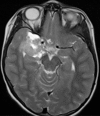

The term desmoplastic infantile ganglioglioma was coined by VandenBerg et al in 1987. In their first report these authors referred to a rare, distinct brain tumor. About 60 cases of desmoplastic infantile ganglioglioma have been described in the literature since its first description. We report a case of a 6-year-old girl who was admitted for seizure without family history. Magnetic resonance imaging scan showed a hypodense area in the right temporal region. A right temporal craniotomy was performed and the tumor was excised. The pathologic examination revealed the diagnosis of desmoplastic infantile ganglioglioma.